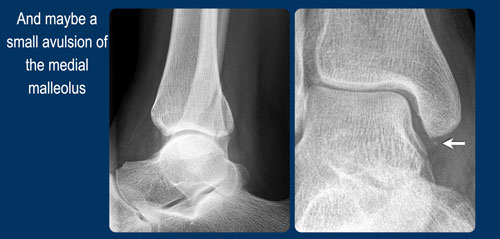

- Gãy bong điểm bám mắt cá trong hoặc đứt các bó dây chằng bên trong (medial collateral bands)

Khi xương sên tiếp tục di chuyển ra sau ngoài, lực căng rất lớn tác động lên dây chằng bên trong (dây chằng delta) sẽ gây đứt dây chằng hoặc bong mắt cá trong.

Đây là gãy xương Weber B giai đoạn 4, thuộc loại không ổn định.